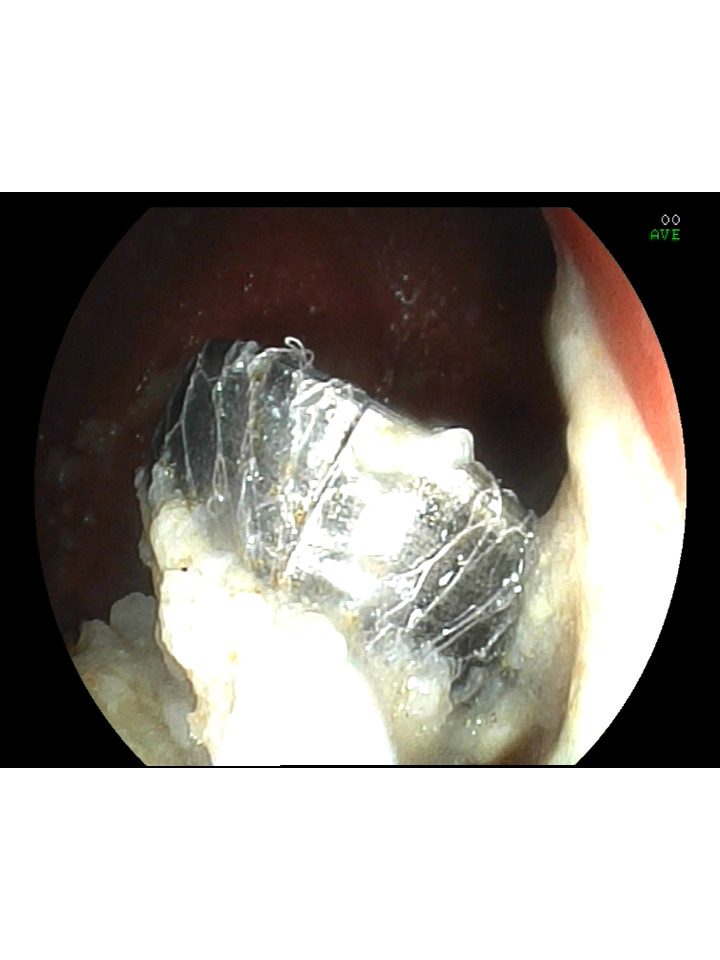

Recently a 10 year old boy who accidentally ingested a foreign body (Metallic cap of table) while playing, developed upper abdominal discomfort. He was brought to emergency department of Tricolour Hospitals. Immediately Upper GI endoscopy was done and foreign body was removed. Hence, the child was saved from risk of intestinal obstruction and major surgical intervention.